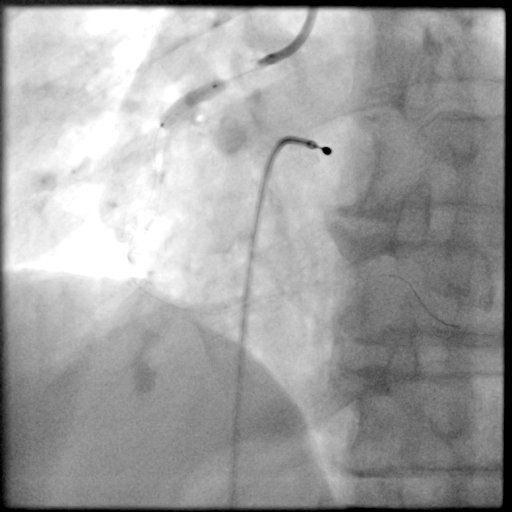

PCI过程-DES植入

由远及近依次送4.0X23mm、4.0X29mm、4.0X13mm DES至病变处串联释放。

PCI过程-支架后造影